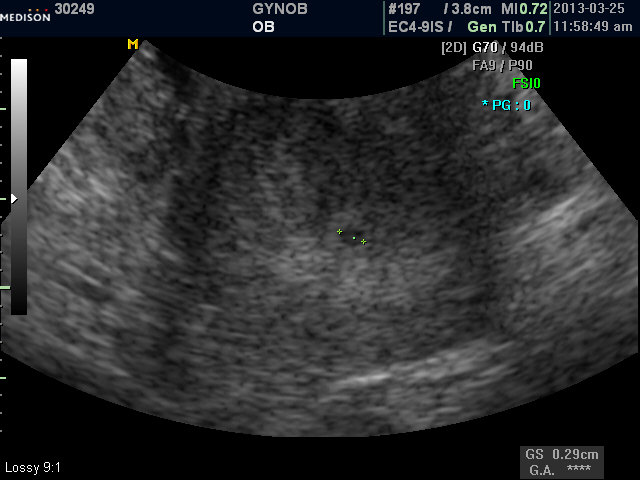

스마트폰 모드|진오비 산부인과